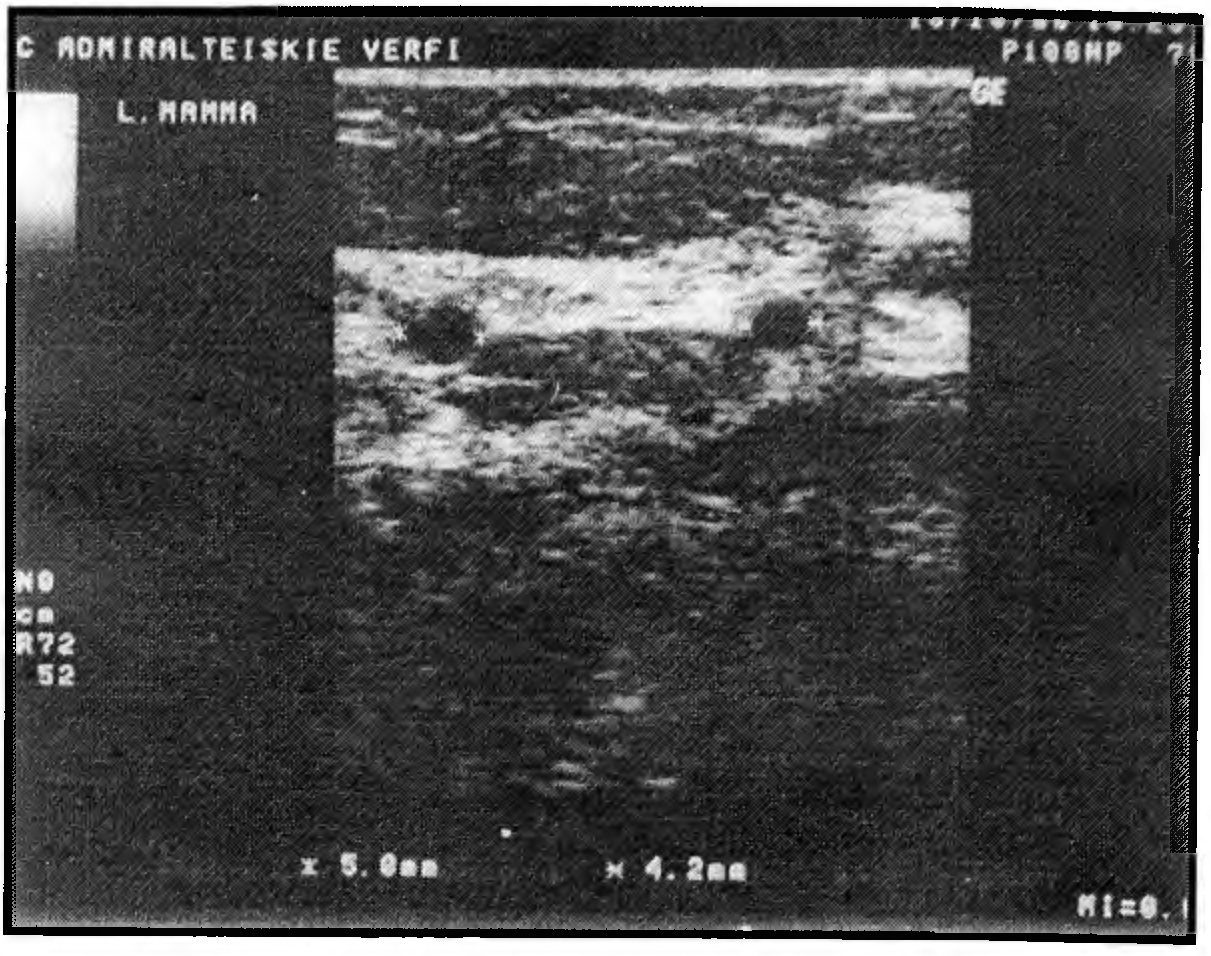

При кистозном варианте доминирующим эхосимптомом является наличие множественных кист, в большинстве случаев выявляемых на фоне фиброзных изменений ткани (повышение показателей эхоплотности) (рис. 7).

Рис. 7. Эхограмма кистозного варианта диффузного ФАМ у пациентки 42 лет. Толщина слоя железистой ткани - 10 мм. Показатели эхоплотности - повышенные (35-37). Мелкие кисты.